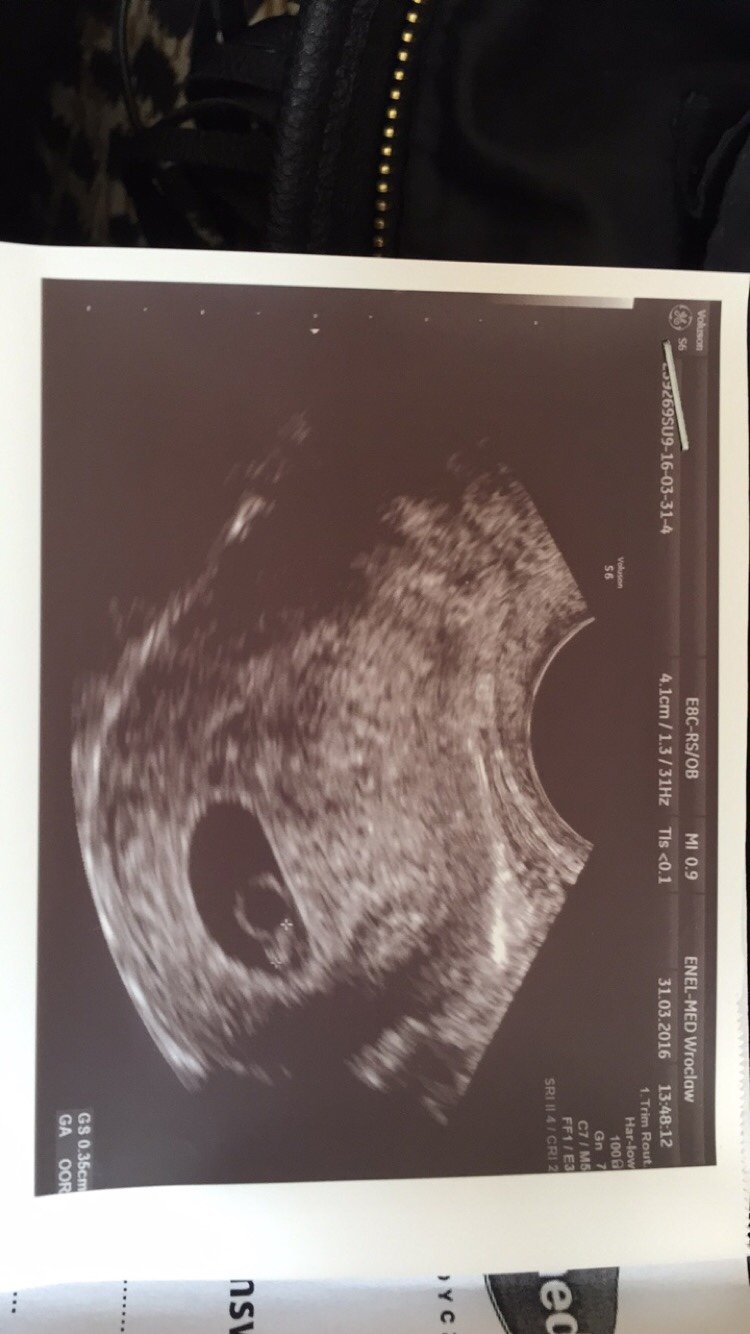

Nasze wizyty u lekarz, USG ...:)

Tamten mi mowil ze wszystko w porzadku i ze mam przyjsc za 2 tyg, czyli 8.04.. Nie chodzi mi o to, ze didzia zmalala, tylko ze pecherzyk zmalal :(

Nie bylam na fundusz, jestem zapisana do enel medu i tam mam pakiet oplacony na prawie wszystkich lekarzy.. Ale mozecie mi powiedziec co ta kobieta miala w glowie zaznaczajac na usg "TO" i mowiac ze to pecherzyk? Bo na ostatnim usg u poprzedniego lekarza "TO" (mierzone jako crl) mialo 0,17 cm a teraz ma 0,35cm...

To to chyba fasolka kochana, koło ciałka żółtego.

GS o to pytasz? To pecherzyk ciążowy..